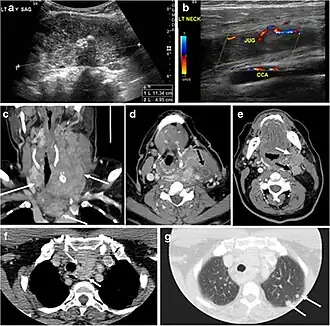

Surgery is the primary mode of treatment for DTCs. Post total thyroidectomy radioactive iodine (RAI) ablation is an option, especially in patients with distant metastasis, tumours larger than 4 cm, or extra-thyroidal disease extension. Ultrasound examination is usually adequate in evaluating primary tumours and cervical lymph nodes. Preoperative cross-sectional imaging with CT or MRI is indicated if there is a concern for local invasion that may alter the patient's staging as well as surgical approach (Figs. 4, 55 and 6)6) . Some thyroid primaries may be small, diffuse, or multifocal and therefore may be occult on imaging (Fig. 4) .[1]

Fig. 4. A 45-year-old male patient presented with anterior mediastinal metastatic PTC lesions and occult primary on imaging. Histopathology examination of the resected thyroid gland revealed micro-foci of PTC; the largest, in the isthmus, measured 4 mm. a transverse greyscale ultrasound of the thyroid demonstrates homogeneous gland with normal echogenicity and size. No focal lesion or micro-calcifications. b Non-enhanced CT scan obtained as part of PET/CT examination shows a heterogeneous, large, relatively dense anterior mediastinal mass (white arrow) with peripheral calcification (arrowheads). Thyroid gland has normal CT appearance with no abnormal FDG uptake (not shown).[1] -

Finally, the possibility of metastatic disease should be excluded. PTCs and medullary thyroid carcinomas tend to metastasize to regional lymph nodes. According to the AJCC/UICC TNM staging system, the nodal stage is classified by site: N1a indicates level VI nodal involvement, including paratracheal nodes; N1b indicates unilateral or bilateral lateral cervical nodal disease or superior mediastinal nodal disease (Figs. 4, 55 and and6)6).[1]

Fig. 7. A 51-year-old female patient post total thyroidectomy for PTC with elevated thyroglobulin measurement. an Axial non-enhanced CT scan of the neck at the level of the thyroid bed demonstrates a well-defined, rounded, homogenously dense soft tissue situated between the trachea and left internal jugular vein (white arrow). b Transverse ultrasound image of the neck demonstrates a well-defined, homogeneous, hypoechoic soft tissue nodule measuring 6 mm (white arrow) with no detected micro-calcifications. Biopsy showed a predominantly residual normal thyroid tissue with micro-foci of PTC.[1] -

Fig. 8. A 48-year-old male patient post total thyroidectomy with PTC recurrence. a Transverse greyscale ultrasound of the neck demonstrates a left thyroid bed heterogeneous, predominantly hypoechoic irregular lesion with calcifications (white arrow). b A spot image of iodine 123 total body scan of the neck demonstrate a focus of abnormal radiotracer uptake at the left thyroid bed (Black arrows) between the annotated markers. c Enhanced axial CT scan of the neck demonstrates an enhancing large left thyroid bed mass (white arrow) with no calcifications. The lesion exerts a mass effect on the oesophagus (black arrow) and is inseparable from the trachea.[1] -

Fig. 9. A 58-year-old male patient with persistence PTC at thyroid bed with hypervascular nodal metastasis. a–c Transverse greyscale and colour Doppler neck ultrasound demonstrate hypoehoic soft tissue in the left thyroid bed (white arrow in a). There are a heterogeneous enlarged lymph nodes at level 2 and 3 with markedly increased vascularity (white arrow in b and c). d–f Enhanced axial CT images of the neck demonstrate a 2.7 × 1.4 cm hypodense soft tissue lesion anterior to the left carotid sheath (white arrow). There are left-sided enhancing abnormal and enlarged lymph nodes at cervical level 2 and 3 (black arrows).[1]